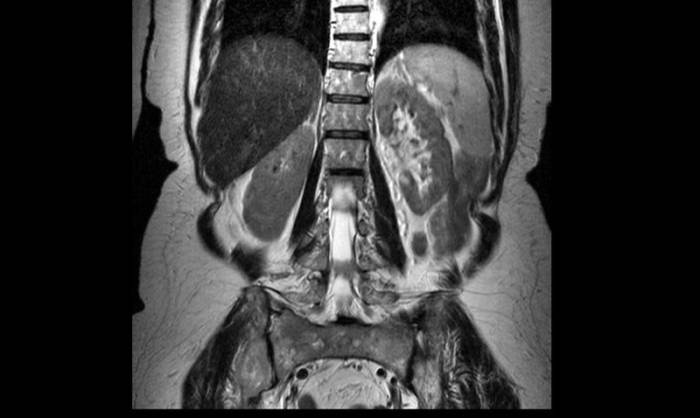

Опухоль спинного мозга на МР-томограмме (обозначена стрелкой)